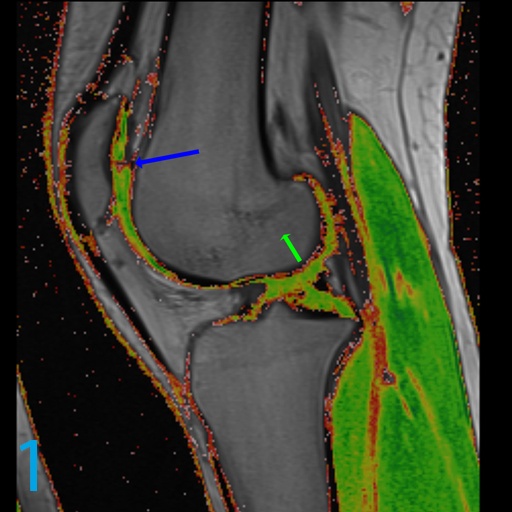

1. What do you call the type of image shown on image 1?

2. What parameter on MRI is varied to achieve such a map?

3. What is the name of the cardinal feature of cartilage organization that is appreciated on such a map?

4. What does the blue arrow indicate on image 1?

1. T2 cartilage map

2. The echo time or TE

3. Stratification. In other words, the deeper portions of cartilage are normally darker on water-weighted images and get lighter as one proceeds more superficially and this translates into a change in color from darker colors and hues to lighter colors and hues. This should remain organized throughout the young knee.

4. Alteration in glycosaminoglycans substance, arrangement, and altered proteogylcan milieu.